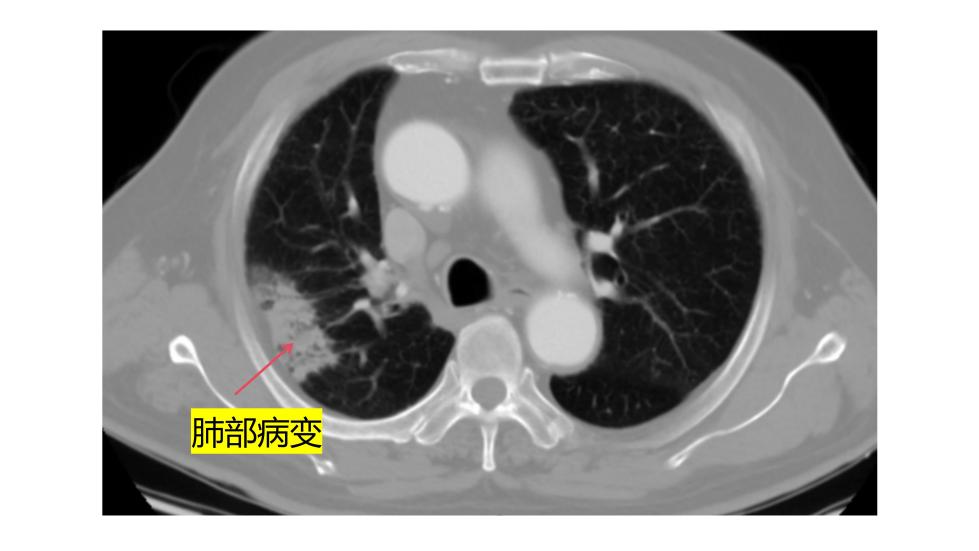

老王的病情发现于2025年底的一次肺部CT检查。检查显示,他的主动脉弓部长了一个累及颈动脉的动脉瘤,随时可能破裂致命。然而,传统的开胸手术需要让心脏停跳、体温降到很低,创伤极大,对心肺功能要求很高。"老人已经78岁了,肺功能又不好,根本耐受不了这种常规开胸大手术。"医院血管外科中心舒畅教授解释。